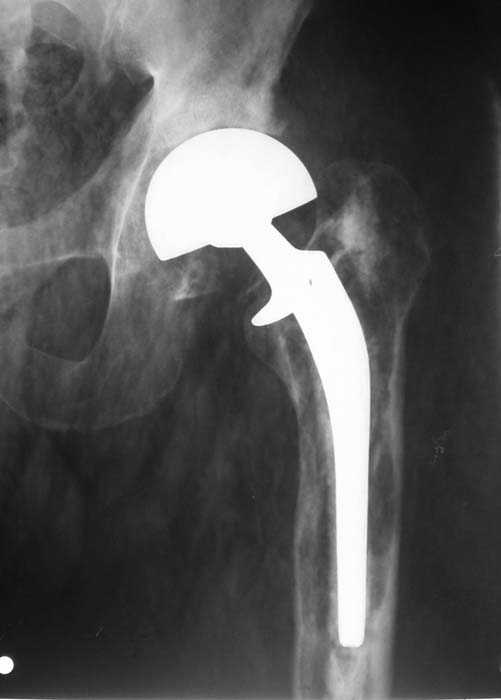

Мужчина, 39 лет.По поводу двустороннего асептического некроза головок бедренных костей последовательно выполнено тотальное эндопроезирование левого (1998 г), затем правого (1999 г) тазобедренных суставов.

Нет никакого смысла делать операцию в два этапа. С чашкой все понятно - стандартный подход с установкой пресс-фит компонента. На бедре имеет

место перипротезный перелом В3 типа - т.е. перелом вокруг ножки с ее нестабильностью на фоне выраженного остеолиза. Решение - доступ к каналу

через перелом с удалением самой ножки, костного цемента и рубцовых тканей. Установка ножки дистальной фиксации (типа Solution), длину ножки

надо определить по шаблону. Минимальный контакт ножки с интактной костью - 6-8 см. Фрагменты проксмального отдела собираются на ножке

эндопротеза, дефекты костной ткани заполняются чипсами (аллографт) и фиксируются кортикальными аллографтами, уложенными дополнительно по типу

"вязанки хвороста" серкляжом. Мы имеем 8 или 10 подобных наблюдений и результатами довольны.